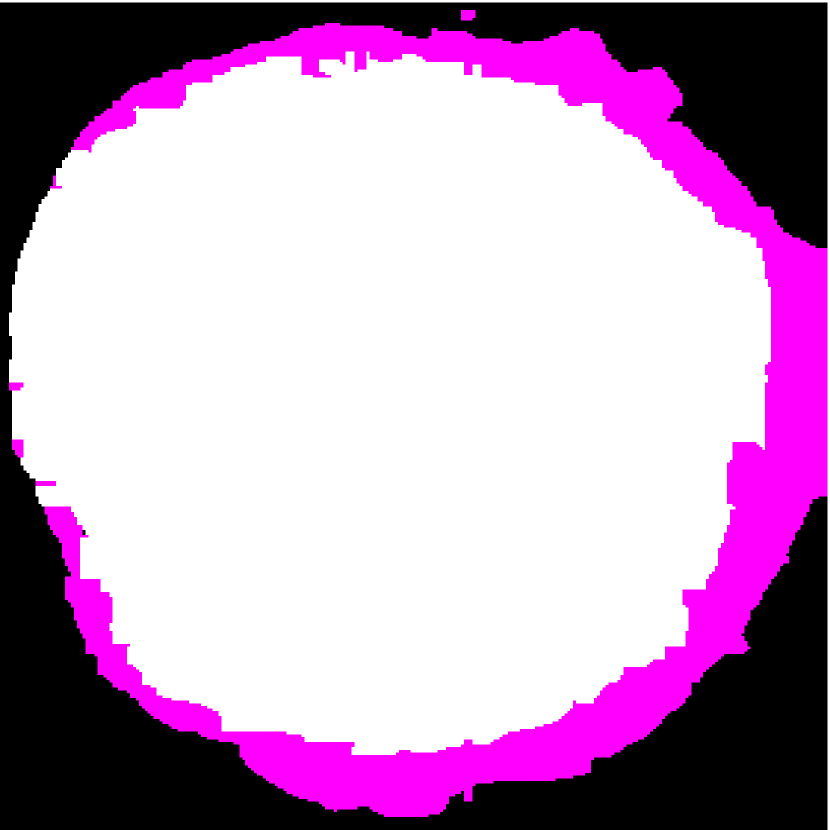

Figure 2: (a) Target HFU image. (b) Manual-segmentation result. (c) The segmentation result obtained by NGC with depth-dependent profile.

Intensity-distribution estimation is another challenge in LN segmentation. To obtain satisfactory segmentation, accurate intensity distributions for the three components of isolated LNs are required. Some clustering algorithms, such as K-means or expectation maximization (EM), may be able to categorize the intensity values of all voxels into three distributions to represent target objects. However, these approaches often yield unsatisfactory segmentation results for larger LNs (Figure 1(c)), where the intensity distribution fluctuates significantly with depth because of acoustic attenuation and focusing effects. In addition, attenuation effects may become so extreme that fat boundaries become invisible. (See the red arrow in Figure 1(a).) To mitigate the attenuation and missing-boundary problems, we used depth-dependent intensity profiles to model the depth-dependent variation of intensity mean and standard deviation in our prior work [11]. Using an expectation-maximization (EM) -based iterative framework, depth-dependent profiles were estimated by a spline-based fitting process from the previous segmentation result, and the segmentation result was obtained by NGC using the estimated depth-dependent profiles. Instead of using an EM-based framework to update profiles, level-set-based approaches can also update profiles during deformation. Bui et al. developed a method, which applied depth-dependent profiles, called statistical transverse slice level-set (STS-LS) [15]. Nevertheless, depth-dependent profiles are unable to deal with intensity inconsistency within the same depth caused by inhomogeneous acoustic attenuation as shown in Figure 2. Figure 2(c) shows the segmentation result obtained using a depth-dependent profile [11]. Compared to the manual segmentation result in Figure 2(b), some fat regions (red arrow) are mislabeled as LNP because the fat on the right (green arrow) at the same depth is much brighter than the fat on the left. In this case, depth-dependent profiles are unable to model the intensity variations accurately. Using local distribution to differentiate LNP and the fat can solve the error caused by intensity inconsistency within the same depth. Bui et al. has used a local-region-based, gamma distribution to segment LNs [13]. Level-set-based methods is good in applying local intensity distributions to differentiate regions. Since level-set-based methods deform the contour gradually, the local distributions can be updated by the boundary accordingly. However, updating distributions in local regions is computationally expensive. Furthermore, using local-region-based distributions with level-set-based methods is likely to result in convergence to a local minimum when the image is noisy. In contrast, GC-based approaches generally set the similarity cost by predefined intensity distributions. Because the boundary is unknown, the local region is hard to be determined in advance.